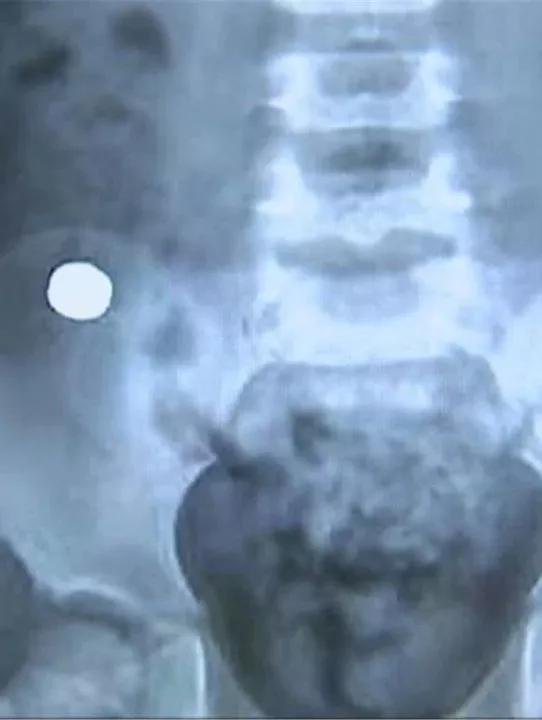

事发后,他们曾经在内蒙古当地医院给孩子拍了CT。异物形状小而圆,大家怀疑很可能是一枚纽扣电池。

家长告诉医生,CT照片显示,异物已经进入到肠道,但孩子没有明显的食欲减退、腹痛症状,因此当地医生建议先观察一下,等待异物自然排出。可6天过去了,异物几乎没有任何移动,家人才着急起来。

长春市儿童医院 消化内科 副主任 罗磊:通过结肠镜做这个手术。我们达到回盲部,也就是小肠和大肠交界处,发现了此异物,但并不是纽扣电池,是一个黑色的磁铁。

医生告诉记者,因为回盲部比较狭窄,正因为磁铁卡在了这个位置,所以未能顺着肠道排出。磁铁停留的这6天,由于异物摩擦,孩子的回盲部已经出现了充血、水肿和糜烂,如果磁铁再不及时取出,很有可能引起内脏损伤、肠道穿孔等并发症。